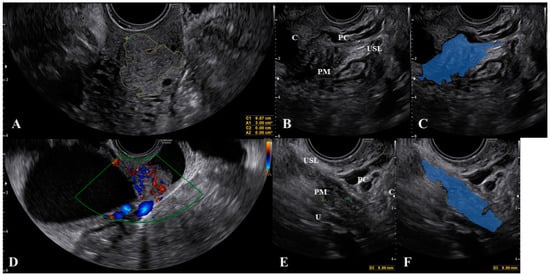

Ultrasound of the Uterosacral Ligament, Parametrium, and Paracervix: Disagreement in Terminology between Imaging Anatomy and Modern Gynecologic Surgery

3. What Ultrasound Should Investigate and Detect